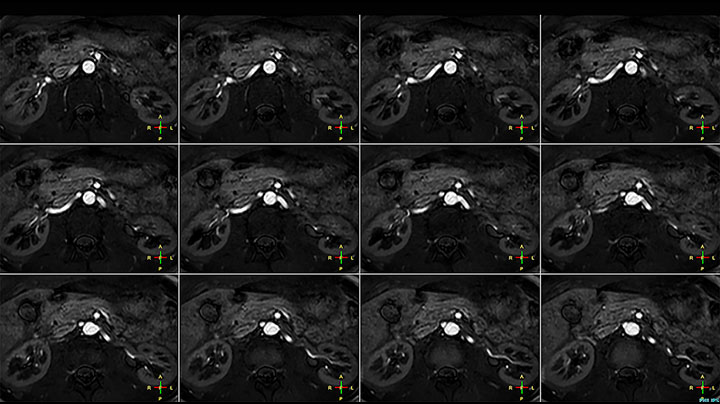

Hier handelt es sich um eine 43-jährige Patientin mit einem supraklavikulären Nervenscheidentumor links. Die Läsion ist auf den STIR VISTA Bildern und auf der MR-Neurographie mit diffusionsgewichteter MRT gut zu erkennen. Die Untersuchung wurde mit Prodiva 1.5T durchgeführt.

Erfasste Voxelgröße: 1,2 x 1,3 x 2,4 mm, rekonstruierte Voxelgröße: 0,7 x 0,7 x 1,2 mm, dS SENSE Faktor: 2, Scandauer: 5:46 Minuten.